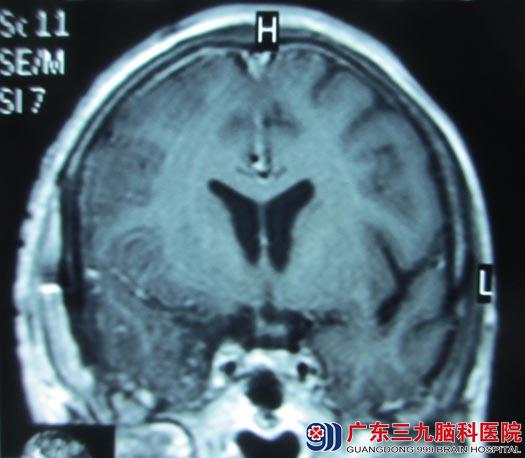

林大妈,60岁。2年前开始出现右眼视力下降,偶有头痛、头晕,未予重视,后症状逐渐加重。3月21日,儿子带着她在医院行头颅MR检查提示“右侧鞍旁占位,直径约2.5cm,考虑脑膜瘤可能”。

入住广东三九脑科医院综合神经外科后,头颅CTA检查显示“右侧鞍旁占位,肿瘤包绕右侧颈内动脉及其分支”。

鲁明主任阅片分析:右侧蝶骨嵴脑膜瘤,肿瘤侵犯海绵窦,包绕颈内动脉及其分支,压迫视神经,手术风险大,主要为术中损伤海绵窦、颈内动脉及其分支,可能导致大出血危及生命,术中损伤视神经致术后视力无法恢复。

术后林大妈的四肢活动正常,复查头部MRI未见明显肿瘤残留,病理检查结果为:右侧蝶骨嵴过渡型脑膜瘤,WHO I 级。